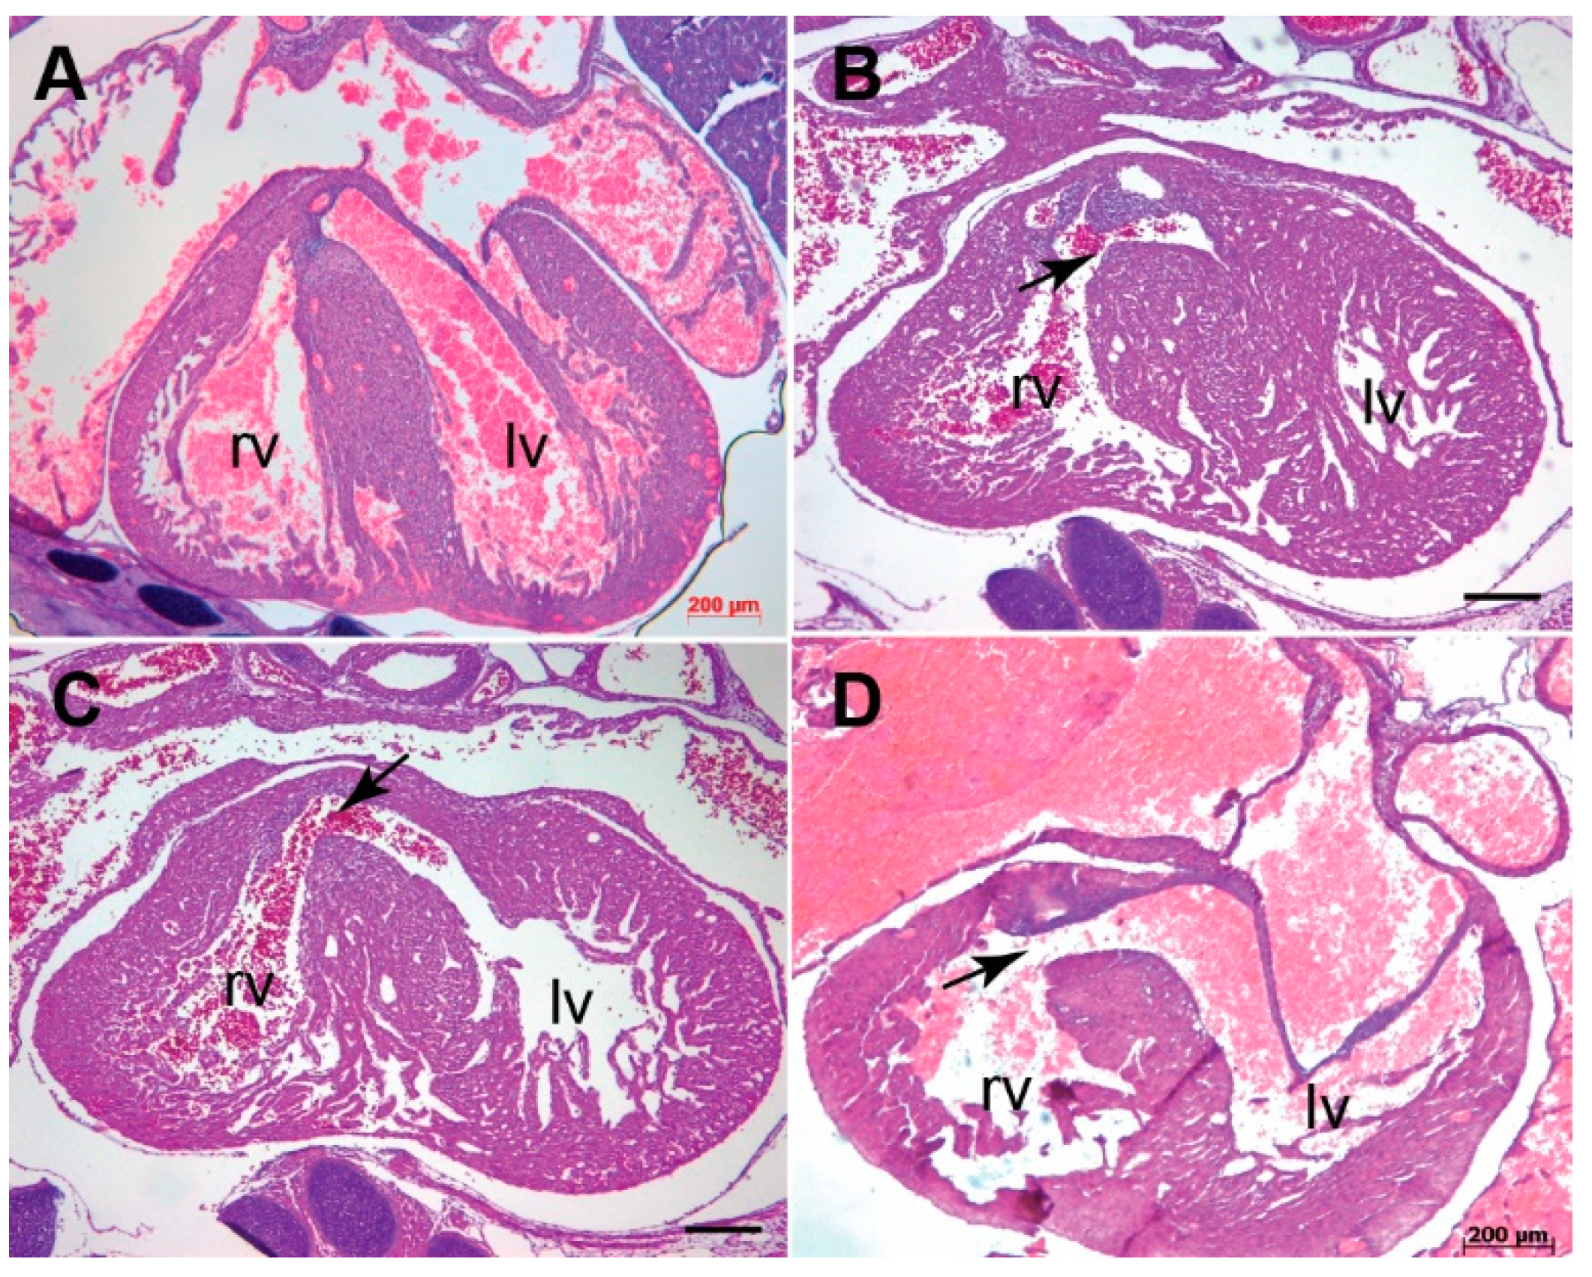

3.1. Systemic Tgfb3 Deletion Disrupts Cardiac Development

3.2. Tgfb3 Deletion Leads to Outflow Tract Cushion Remodeling and Septal Defects

3.3. Tgfb3 Deletion Leads to AV Cushion Remodeling Defects